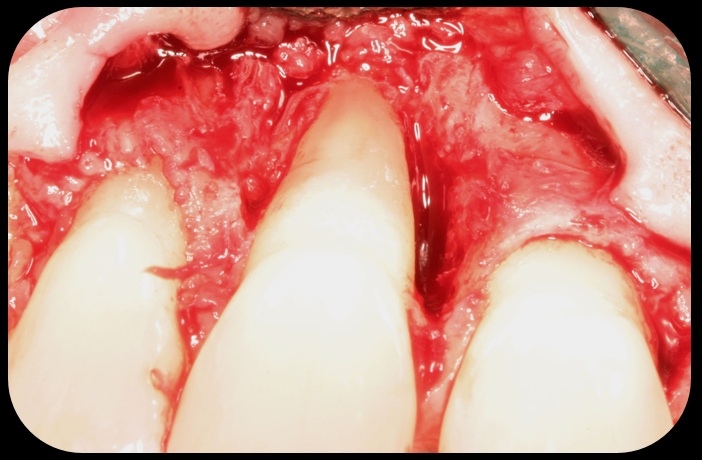

Severe periodontitis lesion.

Fig. 2

Facial bone loss and a mesial vertical defect.

Fig. 3

Then, too, are opportunities to prepare the site for regeneration by coupling therapies, applying an enamel matrix derivative, along with traditional bone grafts of demineralized freeze-dried bone allograft; potentially, gains in attachment with minimal probing depth and retained papilla may avoid the need for an implant (Figure 2 through Figure 7).